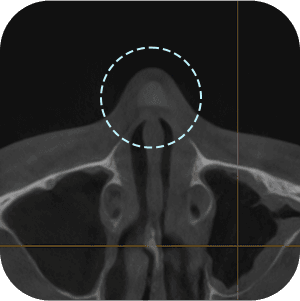

The implant information from the previous surgery is checked

Functional problems such as a deviated septum are checked for

The current implant location is checked

Nasal CT scan, is it necessary?

ASince this is a revision surgery,

a more precise diagnosis is a must!

external appearance and internal functional

problems of the nose are accurately

diagnosed through 3D-CT.